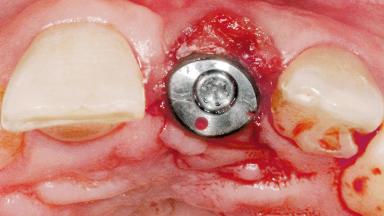

Type of Implants One-Piece

Attachment One-Piece

Bone Augmentation Horizontal|Staged

Augmentation Materials Xenogenous|Membrane

Soft Tissue Grafting Simultaneous